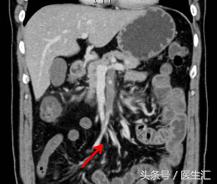

到晚上9:30的时候,患者又出现上腹部腹痛,而且腹痛呈持续性,伴恶心呕吐2次,呕吐呈非喷射状,呕吐物为胃内容物,解黄色水样便一次。夜班医生给与耐信(埃索美拉唑钠)抑酸,得舒特(匹维溴铵)解痉治疗,腹痛不能缓解。再次复查电解质+淀粉酶正常;血常规白细胞和中性粒细胞增高,其他正常。结合患者腹痛、恶心呕吐、水样便,症状很像急性胃肠炎,所以给与左氧氟沙星(左克)抗炎治疗,同时用654-2解痉等治疗。但是患者持续性腹痛没有明显缓解,第7天凌晨2:00夜班医生查体全腹部平软,但是上腹部有一点点轻压痛,无反跳痛,麦氏点无压痛,夜班医师给与654-2解痉处理,但是效果还是不满意。所以做了一个中上腹CT平扫示:肠系膜上动、静脉周围渗出性改变,建议增强扫描。

第7天凌晨2:00夜班医生查体全腹部平软,但是上腹部有一点点轻压痛,无反跳痛,麦氏点无压痛,夜班医师给与654-2解痉处理,但是效果还是不满意。所以做了一个中上腹CT平扫示:肠系膜上动、静脉周围渗出性改变,建议增强扫描。第7天早上10:00做中上腹增强CT示:肠系膜上动脉内低密度影,考虑附壁血栓形成,局部管腔重度狭窄。这个时候这个患者的诊断应该来说已经很明确了。于是请了相关科室的医生进行会诊,决定进行经皮选择性肠系膜动脉造影+肠系膜动脉溶栓术。患者溶栓导管行脉冲式注射尿激酶溶栓,患者术后24h出现便血4次,200ml/次。